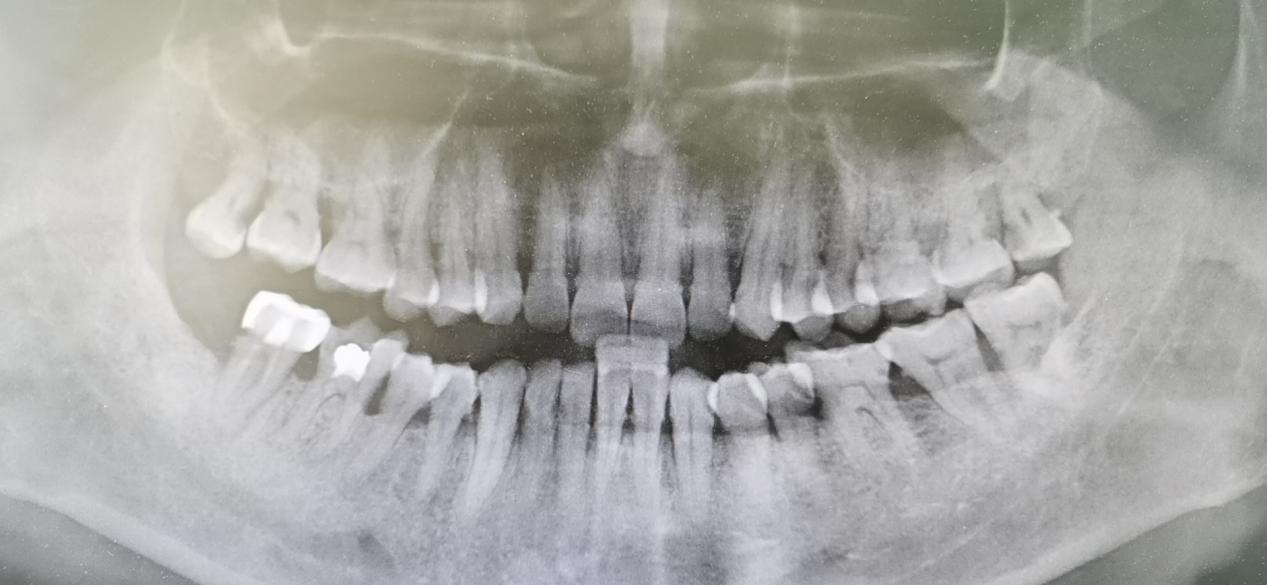

就诊后,首先查看了患者口腔情况,当老人张开嘴,可见牙龈红肿,大量牙石覆盖在牙根部和牙齿缝隙,而且牙齿质地松脆,用探针触及可见出血沿牙龈缘扩散,并溢出牙龈沟,牙周袋深度约为4~6mm。于是进一步安排患者完善曲面断层平,检查结果提示全口牙槽骨水平吸收至根1/3-1/2。

本次就诊的患者就有典型牙周袋形成、牙齿松动、探及出血的表现,而且完善曲面断层平可见牙槽骨吸收,因此明确诊断为牙周炎。鉴于患者口腔情况较差,决定予以全口牙洁治+口腔卫生宣教,并视情况决定洁治后是否要进行牙齿翻瓣术,以消除牙周袋。